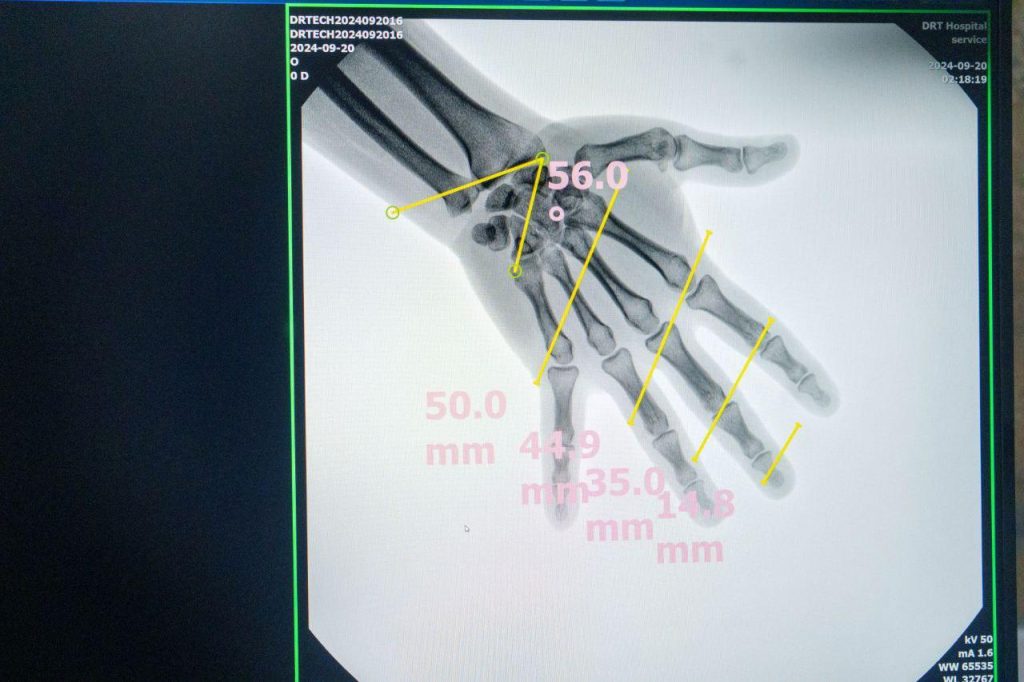

Системи EXTRON 7 з С-аркою експертного класу дають можливість знаходити дрібні уламки від снарядів для їх подальшого вилучення.

Завдяки цьому обладнанню медики зможуть оперативніше надавати допомогу херсонцям при мінно-вибухових травмах.